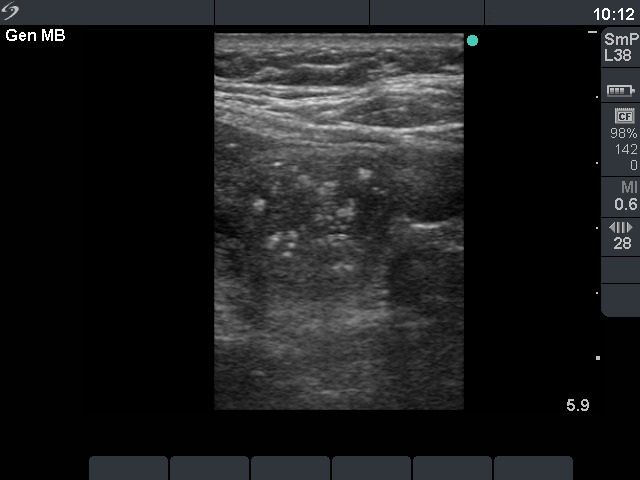

First examination (first row of images)

Clinical data: a 56-year-old man was referred for an evaluation of a recurrent nodular goiter. He was operated 14 years ago, histopathology resulted in benign, hyperplastic nodules. He had no complaints.

Palpation: a multinodular goiter.

Functional state: euthyroidism (TSH 0.69 mIU/L, FT4 12.4 pM/L).

Ultrasonography: both thyroids were enlarged and echonormal. There were multiple, moderately hypoechogenic nodules in both lobes. There was a hypoechogenic nodule in the central part of the left lobe which presented hyperechogenic patches containing bright, hyperechogenic punctate granules. This pattern is similar to that observed in medullary cancer. The vascularization was not specific.

FNAC: was repeatedly not diagnostic.